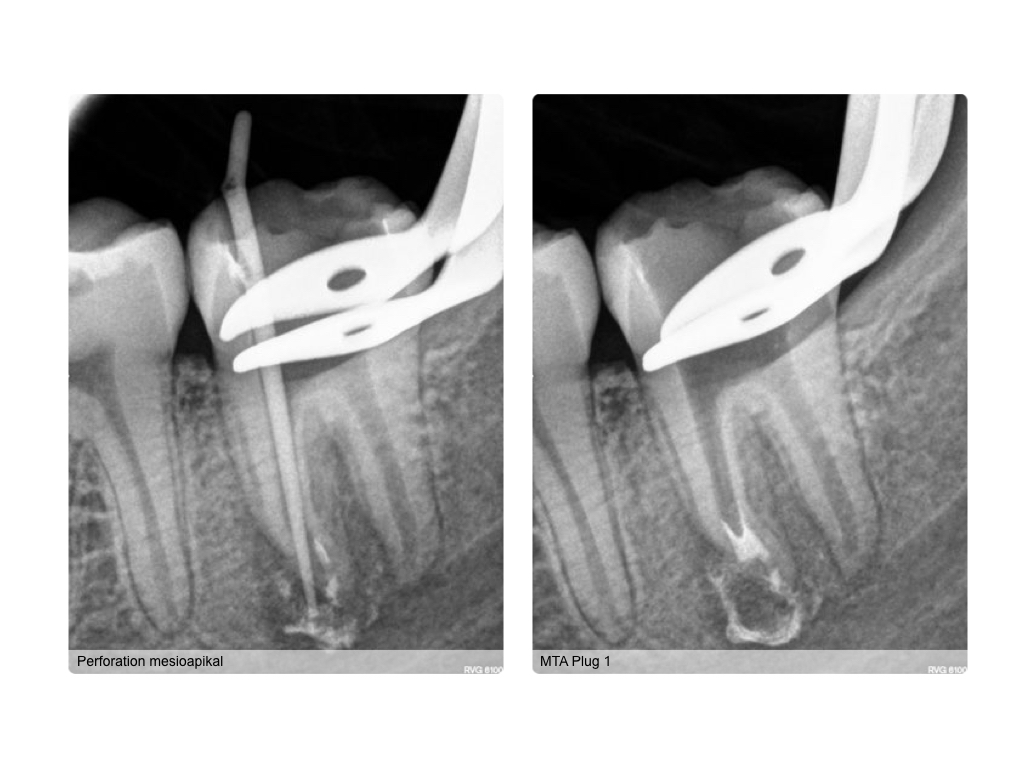

WS_Fallvorstellung11_2_16.013 Veröffentlicht 15. Februar 2016 am 1024 × 768 in Kofferdam – die einfachste Lösung (2)